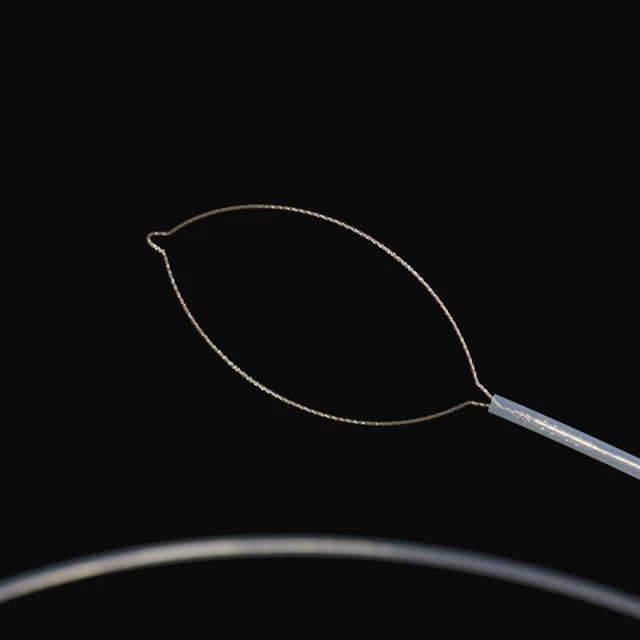

خال اٽاتو

fg -28 -25 ڊي 2 |

2.6 |

2.8 کان وڌيڪ يا برابر آهي |

2300 |

25 |

نيٽ سان گڏ |

|

fg -28 -30 ڊي 2 |

2.6 |

2.8 کان وڌيڪ يا برابر آهي |

2300 |

30 |

نيٽ سان گڏ |